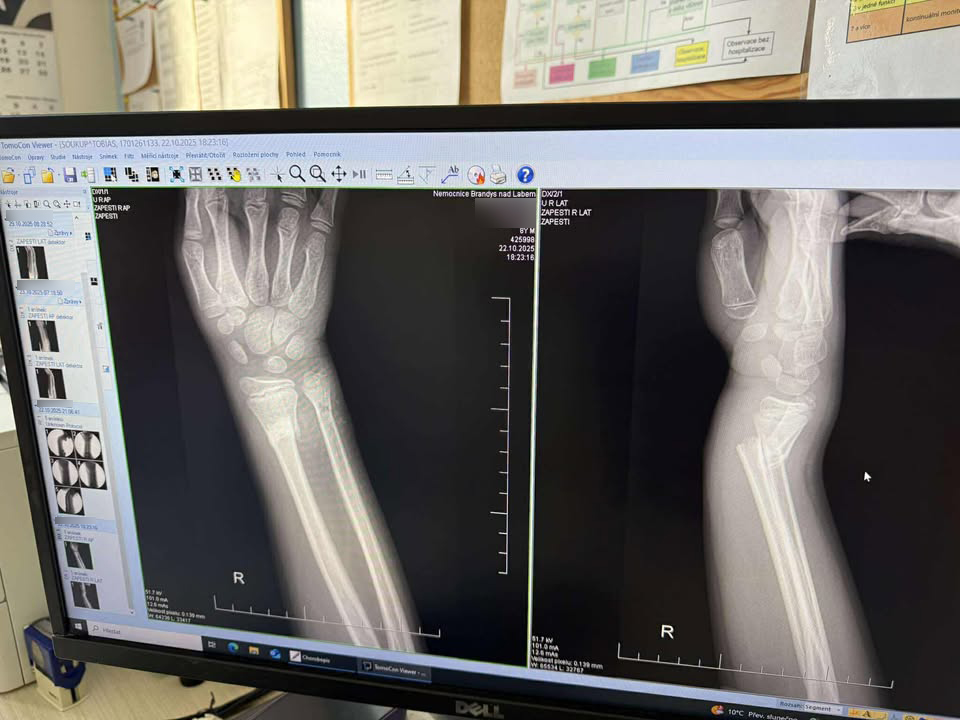

Podle výpovědi však měl mladík v jednu chvíli kopnout s takovou silou, že míč narazil do ruky a způsobil dítěti zlomeninu obou předloketních kostí. Mladý muž pak měl odejít, aniž by se zajímal o stav chlapce. Matka následně vzala syna nejprve do brandýské nemocnice, která je však odeslala na dětskou chirurgii na pražskou Bulovku. Lékaři chlapce operovali a nechali jej v nemocnic přes noc. Ve středu bude muset na další operaci, protože chlapci se ruka zhoršila a je potřeba použít dráty, aby ruka srostla.